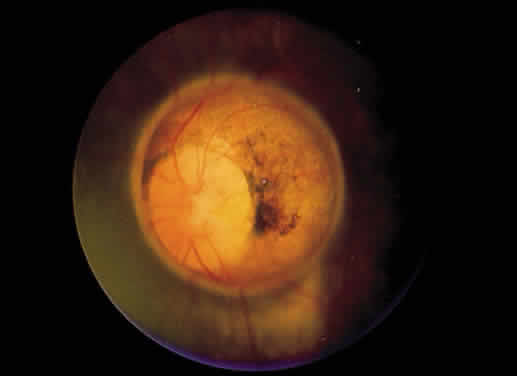

Leber's congenital amaurosis accounts for about 10% of congenital blindness and at least 5% of all inherited retinal dystrophies.202,203 The fundi may be normal in this bilateral disease, but when they are abnormal, they include diffuse pigmentary stippling, pale optic nerves, or both (Fig. 25A through C). Blond fundi also may be seen. Other ocular associations may include cataracts, nystagmus, and hyperopia.204,205

Fig. 25. A. Fundus of a 4-year-old child with Leber's congenital amaurosis. Diffuse pigmentary changes are present in the macula, the optic disc is slightly pale, and the retinal arteries are somewhat narrowed. The child has nystagmus, and there was no central fixation in either eye. B. Fluorescein angiogram of A reveals a pattern of mottled hyperfluorescence better delineating the posterior-pole retinal pigment epithelium disturbance. C. Peripheral fundus photograph shows more marked pigmentary changes. D. The electroretinogram is flat in each eye. (Courtesy of Dr. William Tasman)

The children are usually blind, typically with visual acuity ranging from 20/200 (6/60) to hand motions, or become so during the first year of life. Severe night blindness, and occasionally photoaversion, also is present.206 Roving eye movements may be apparent because of the poor visual acuity.

The electroretinogram is crucial for making the diagnosis and is either flat or shows only minimal responses (see Fig. 25D). This disease is autosomal recessive, and it may represent a type of retinitis pigmentosa, since children with a progressive form may develop fundi identical to the typical retinitis pigmentosa fundus by the middle childhood years.205,207 It is thought that the impaired development or extremely early degeneration of photoreceptors is related to a mutation on chromosome 17, which causes impaired production of a retinal guanylate cyclase.203,208,209